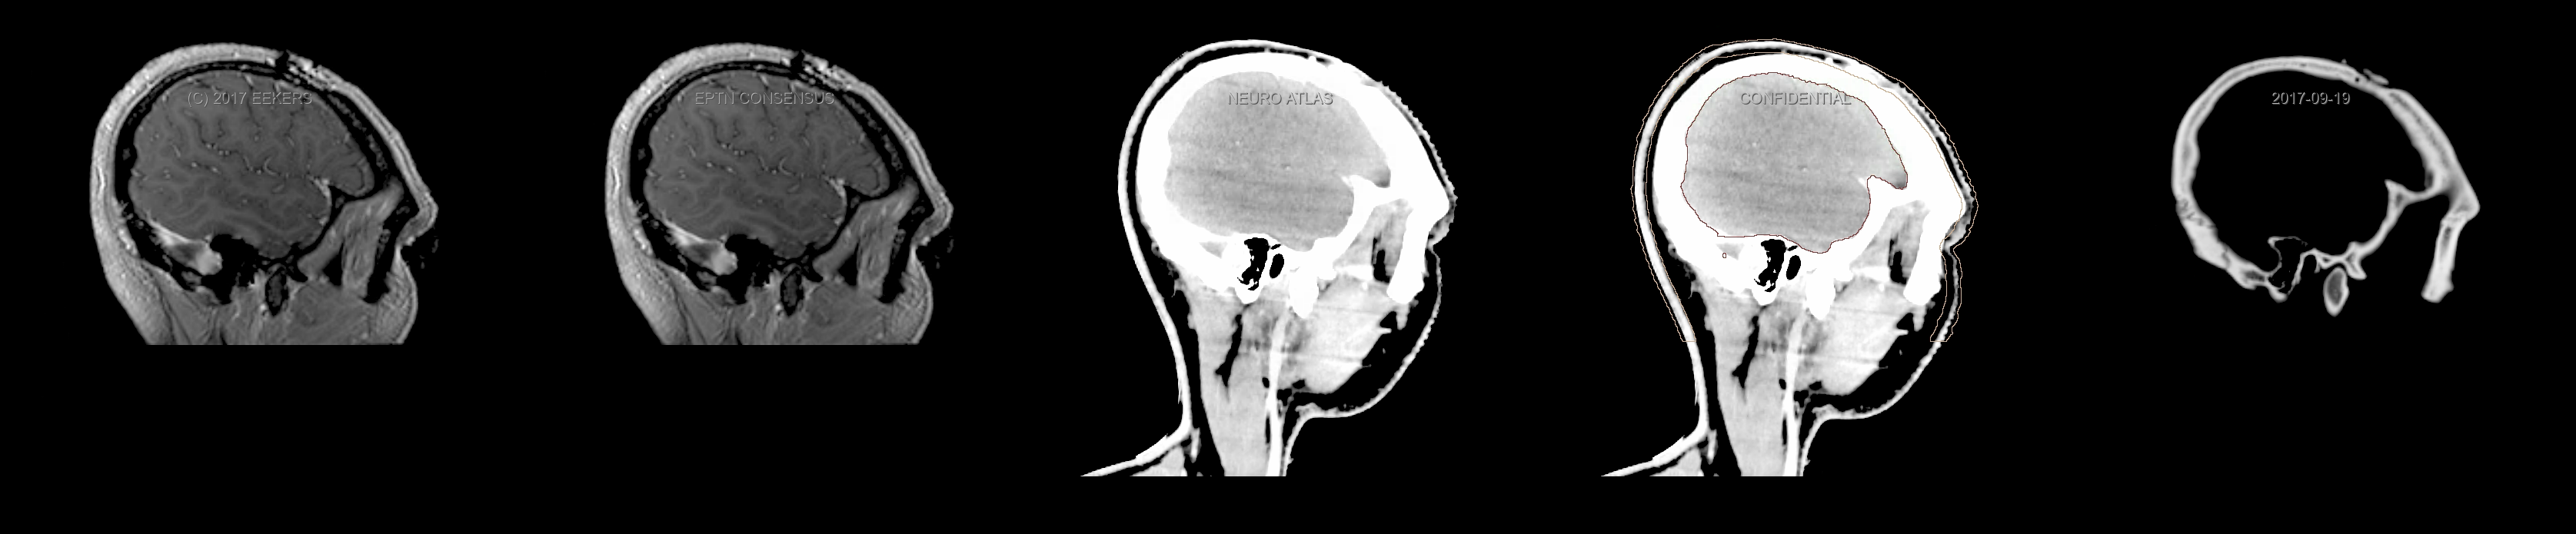

Three-dimensional delineation of the fifteen consensus OARs for neuro-oncology are shown on CT and 3 Tesla (3T) MR images (slice thickness 1 mm with intravenous contrast agent). All are presented in transversal, sagittal and coronal view.

From left to right: MR without structures, MR with structures, CT (WW/WL 120/40) with structures, CT (WW/WL 120/40) with Brain and Brainstem Surface, CT (WW/WL 1500/120)with structures